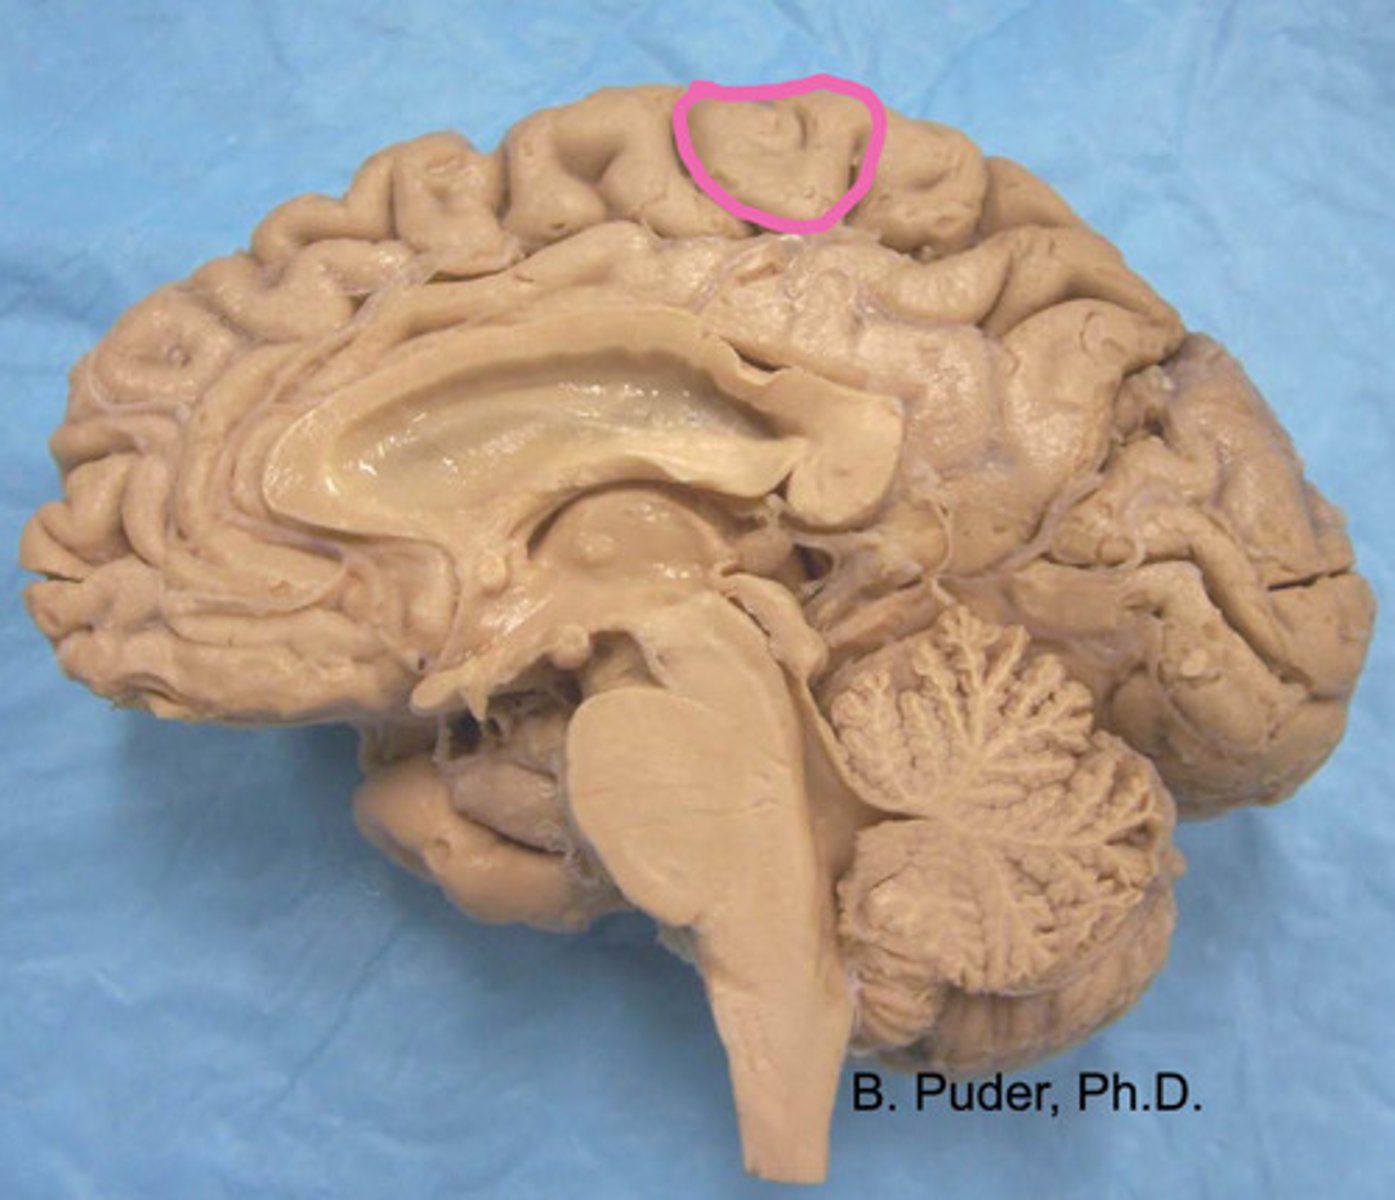

pre-central gyrus

label

paracentral lobule anterior portion

Which brain area is motor control to the contralateral knee, leg, and foot?

precentral gyrus

Which brain area is motor control to the contralateral from head to hip?

postcentral gyrus

Which brain area is somatosensation control to the contralateral from head to hip?

paracentral lobule posterior portion

Which brain area is somatosensation control to the contralateral from knee to foot?

paracentral lobule